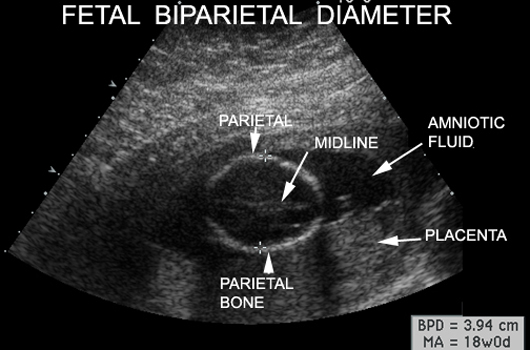

Items Measured by Ultrasound |

Measurements |

Fetal Head Circumference |